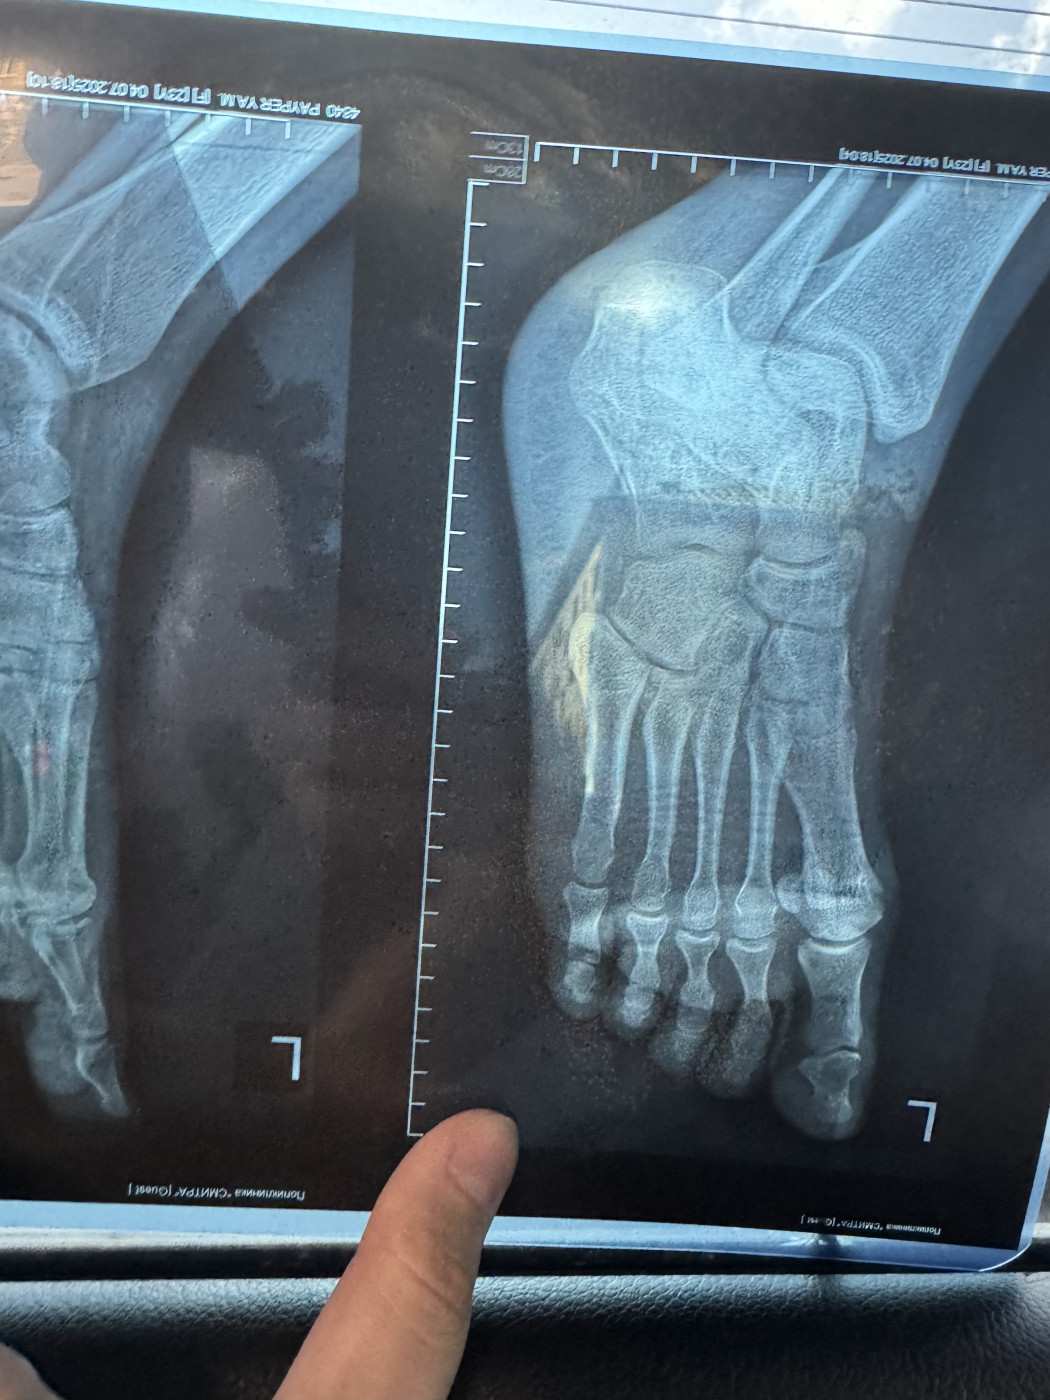

Жмет пластиковый ортезДобрый день! 3 ноября я сломала пятую плюсневую кость на левой ноге, перелом без смещения. Мне наложили гипс. 15 ноября после повторного рентгена (снимок от 15 ноября на фото) мне наложили пластиковый ортез ordect и сказали, что я могу ходить с опорой на пятку. Но этот ортез мне жмет, мизинец очень плотно прижат к другим пальцам. |